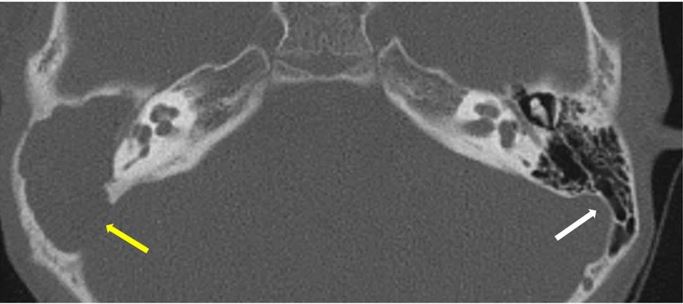

HRCT imaging of acquired cholesteatoma

The authors of this review analyse the various HRCT imaging features of acquired cholesteatoma, a reporting template, and briefly discuss the imaging of the post-operative ear.